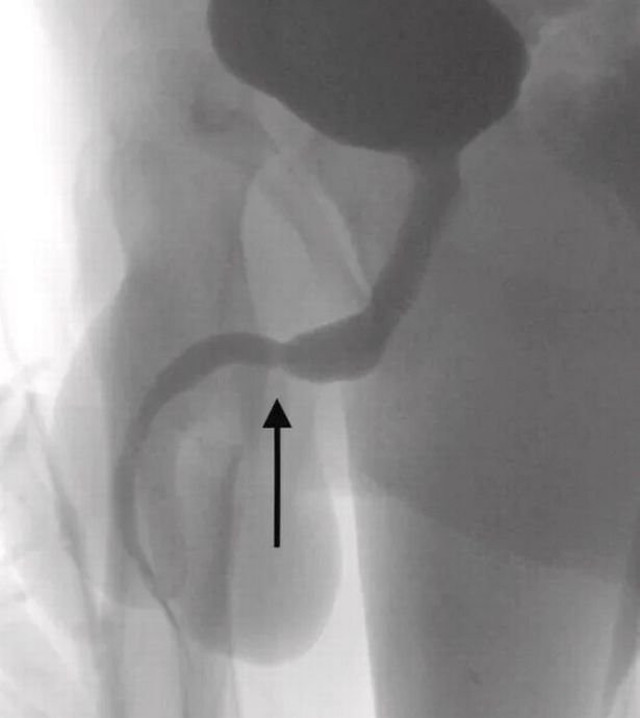

Abone olİngiltere'de tıp literatürüne giren olayda hastaneye kaldırılan 15 yaşındaki çocuk durumu doktorlara anlattı. Gencin röntgen sonucunu inceleyen bilim insanları ise şaşkına döndü. “Cinsel deney” uğruna sağlığını riske atan gencin penisinden USB kablo zorlukla çıkarıldı.

Ameliyatı gerçekleştiren doktorlar durumu kamuoyuna hazırladıkları bir rapor ile duyururken, USB kablolarının vücut içinde düğüm olduğunu ve bu sebeple ameliyatın büyük bir zorluk içerisinde gerçekleştiğini açıkladı.

Science Direct isimli medya platformunun Urology isimli bilimsel dergiden hazırladığı haberde yer alan bilimsel araştırmada olayın 2021’de meydana geldiği belirtildi. Doktorların kaleme aldığı bilimsel araştırmada, “Vücuda yerleştirilen cisim derin doku üzerinden çıkarıldı. Kablolar penis ucundan çıkarıldı” denilirken ismi açıklanmayan gencin cinsel deney için bunu yaptığı ve herhangi bir zihinsel rahatsızlığı olmadığı da duyuruldu.